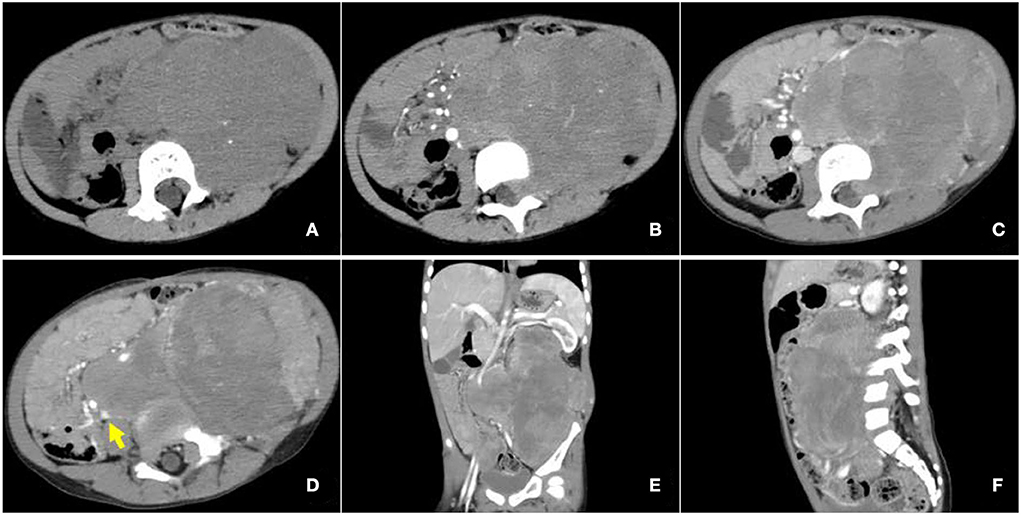

34-year-old Woman With Retroperitoneal Rhabdomyosarcoma.... | Download

www.researchgate.net

www.researchgate.net

retroperitoneal rhabdomyosarcoma year contrast axial demonstrates bilateral extention